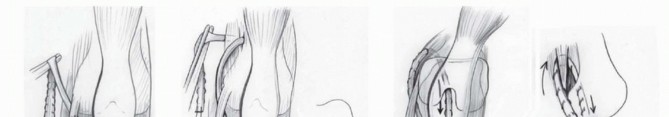

If performed independently, the same midlateral straight incision is used. The anterior and posterior margins of the fascia lata are incised longitudinally. The fascia lata is transected as proximally as possible and reflected distally until its insertion onto the tibia ( TECH FIG 6A ).

The fascia lata is split into two longitudinal strips to make two ligaments. A Krackow whipstitch5 is used to run a nonabsorbable suture from the free end of the fascia lata toward the tubercle of Gerdy in a tubular fashion ( TECH FIG 6B ).